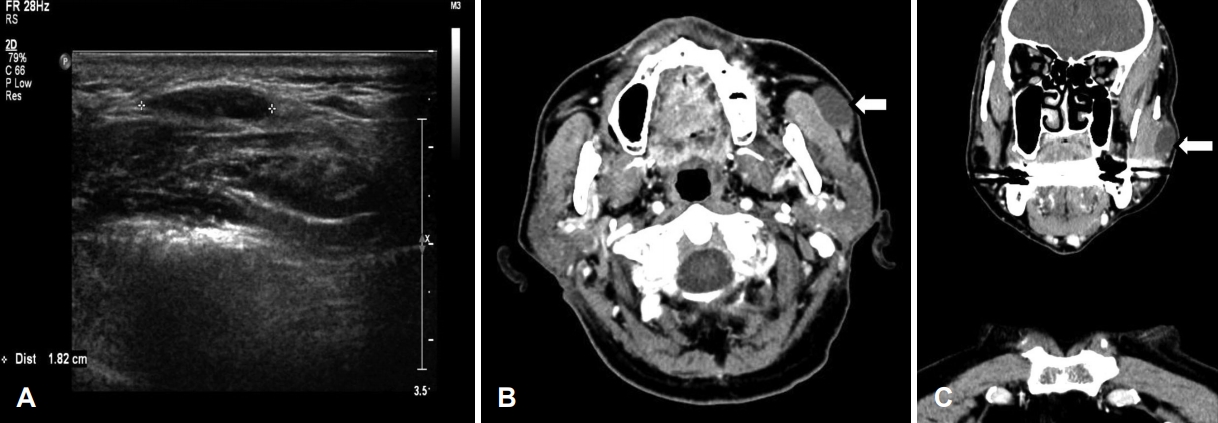

영상 평가를 위해 시행한 초음파 검사에서 교근의 천층에 1.8×1.4×0.4 cm 크기의 뚜렷한 저에코 음영을 보이는 난원형 종물이 관찰되었다(Fig. 2A). 전산화단층촬영에서는 동일한 위치에 2.0×1.3×1.8 cm 크기의 조영 증강되지 않는 저음영 종물이 보였다(Fig. 2B and C). 조직학적 진단을 위해서 초음파 유도하에 종물 내부의 액체를 흡인하고, 낭벽 주변과 고형 성분으로 판단되는 부위에서 중심 생검을 시행하여 “분절된 소수의 침샘 조직”으로 보고 받았다. 환자의 연령, 전신상태 및 수술 합병증 등을 고려하여 에탄올 경화 요법을 시행하기로 하였다. 중심 생검이 가지는 진단의 일부 부정확성을 배제하기 위하여 시행한 두번째 중심 생검에서는 “변성된 조직을 동반한 호산성 과립세포(oxyphilic cells with degenerated tissue)”로 보고되었다(Fig. 3). 두 번의 생검 결과와 영상 소견 등을 종합해서 부이하선에 발생한 양성 낭종성 종물로 진단하였다.

NotesAuthor Contribution Conceptualization: Seung Woo Kim. Formal analysis: Beom Mo Koo. Investigation: Beom Mo Koo. Methodology: Moon Seung Beag. Supervision: Seung Woo Kim. Validation: Mi Ji Lee. Visualization: Mi Ji Lee. Writing—original draft: Moon Seung Beag. Writing—review & editing: Seung Woo Kim. Fig. 1.Facial photographs before (A) and after treatment (B). It shows a 1.6×1.4 cm sized well-margined ovoid mass on right mid-cheek area (arrowheads) (A). It shows no definite delineation of mass in same region (B). Fig. 2.Initial imaging studies. Transverse scan of neck ultrasonography reveals 1.8×1.4×0.4 cm sized well-margined ovoid hypoechoic mass superficial to masseter muscle (asterisks) (A). Enhanced neck CT scan reveals non-enhanced low density mass on right mid-cheek area (arrows) (B, C). Fig. 3.Findings of core needle biopsy. Each of color box means the areas of oxyphilic cells and degenerated tissue (H&E stain, ×100) (A). It shows a typical oxyphilic cell (arrow) (H&E stain, ×400) (B). H&E: hematoxylin & eosin. Fig. 4.Post-treatment neck CT scans after one week (A) and ten weeks (B). It shows a collapsed cystic wall (arrowhead) with heterogenous enhancement of left masseter muscle (arrow) (A). It reveals no significant interval change of fused cystic wall (arrowhead) with normal density in left masseter muscle (B). REFERENCES1. Toh H, Kodama J, Fukuda J, Rittman B, Mackenzie I. Incidence and histology of human accessory parotid glands. Anat Rec 1993;236(3):586-90.